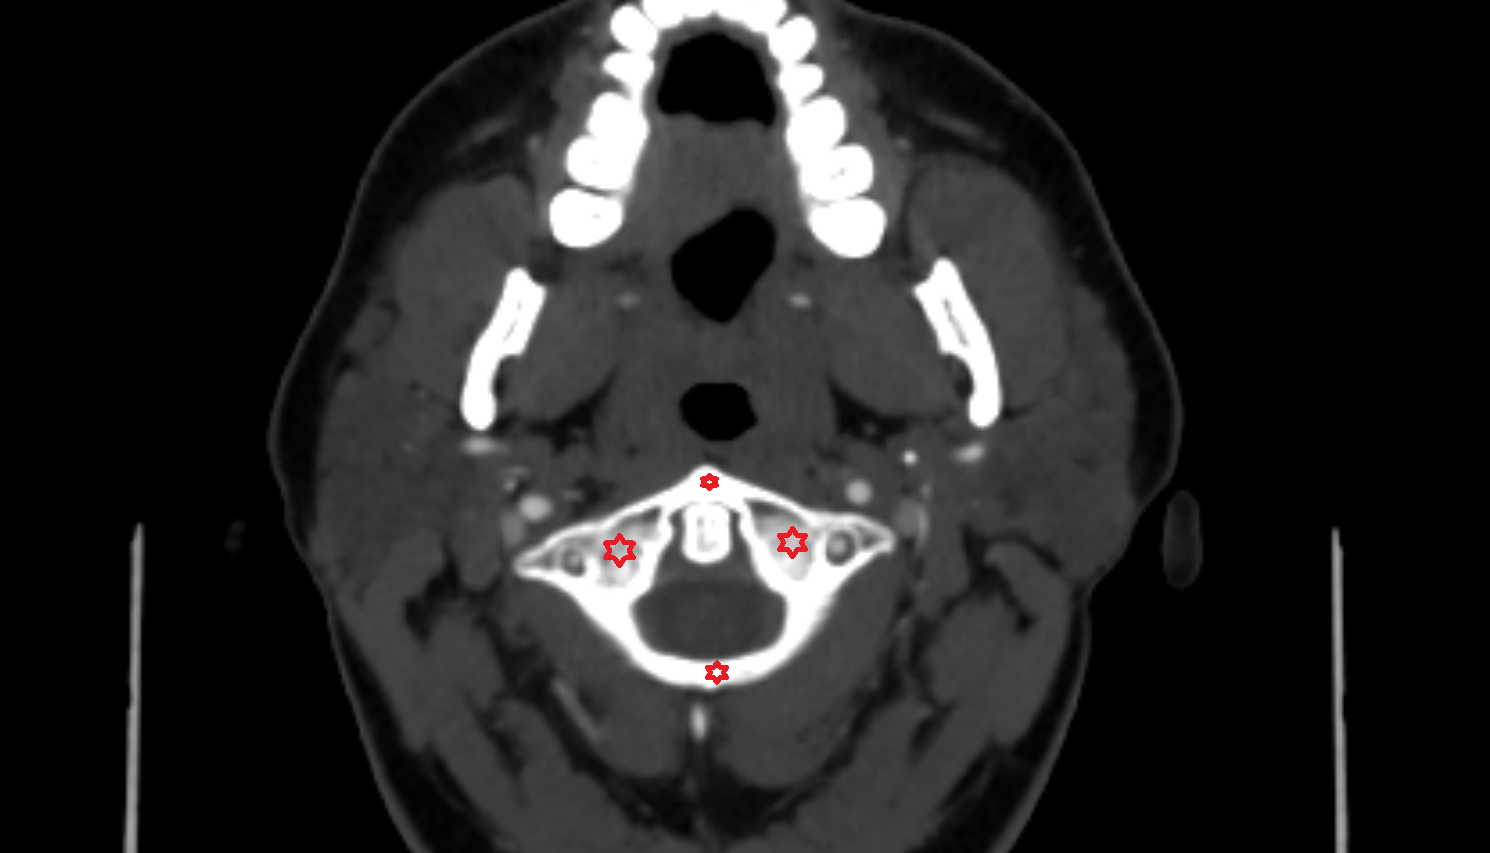

- Median atlantoaxial joint

- Dens of axis

- Lateral mass of atlas